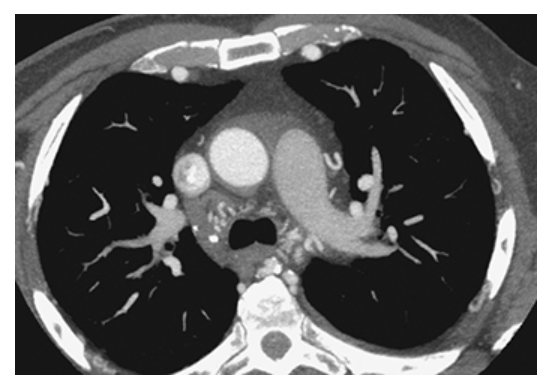

Type A Dissecting Aneurysm. Axial CT with IV contrast demonstrates a Type A aortic dissecting aneurysm involving both the ascending and descending thoracic aorta showing a double lumen separated by the intimal flap.